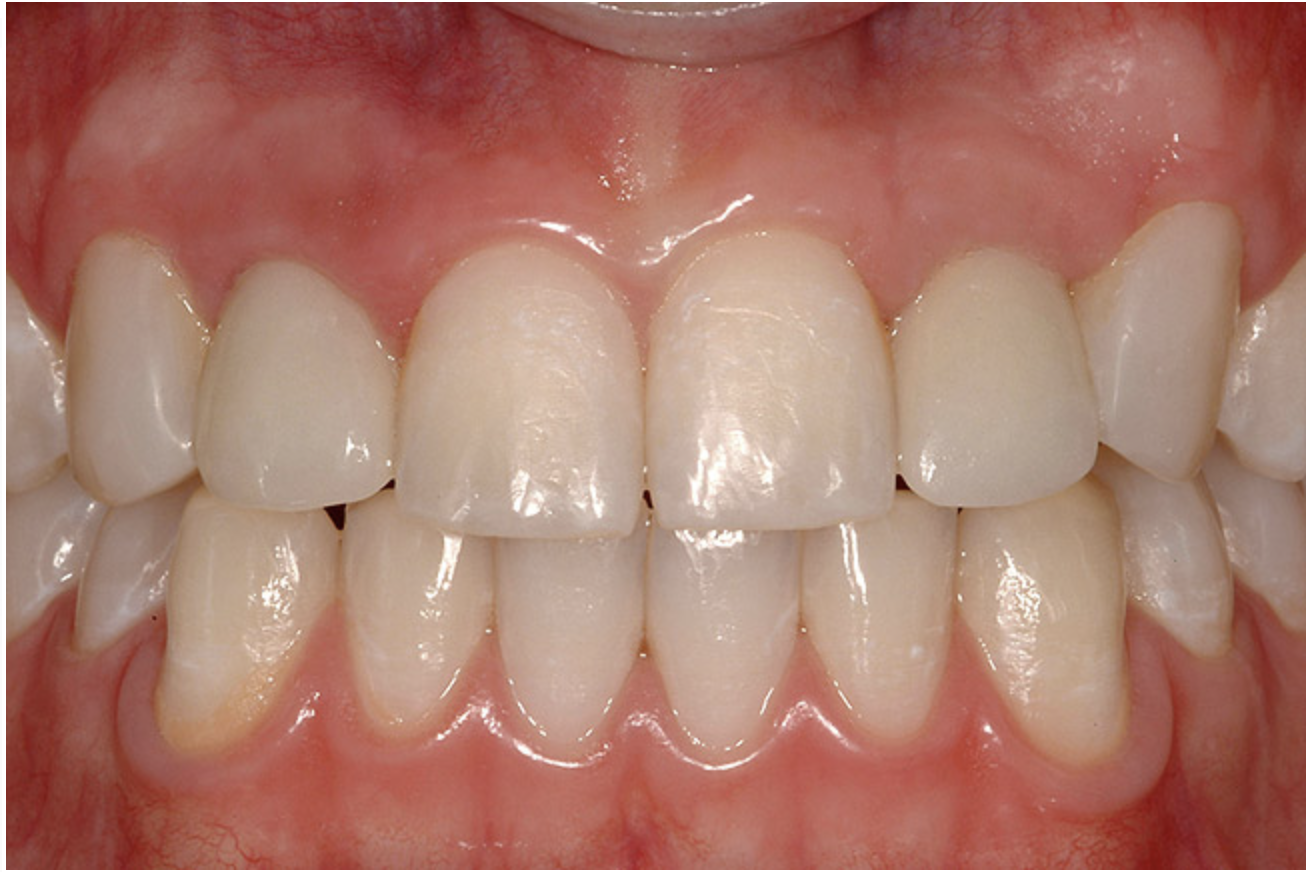

The transitional titanium abutments were left in place for 8 weeks. During this time, the morphologically shaped, computer-milled abutments supported the interproximal tissue and developed the desired emergence profiles. The computer-milled abutments were created to accommodate the adjacent teeth and opposing occlusion, and to aid in the fabrication of the final porcelain-fused-to-metal (PFM) restorations (Figure 20A and Figure 20B). The final crowns were delivered 4 months after implant placement. The radiograph of the emergence profile confirmed the seamless fit of the abutment-implant-crown interfaces (Figure 21). The final restorations were esthetic, functional, and met the needs of the patient (Figure 22A). The re-establishment of the interdental papilla completed the careful transformation of the flat alveolar crestal tissue into a proper emergence of the clinical PFM crowns, indistinguishable from the surrounding dentition (Figure 22B).

Figure 22a  The final restorations are indistinguishable from the surrounding dentition, demonstrating good emergence and re-creation of the interdental papillae.

Figure 22a

Figure 22b  The final restorations are indistinguishable from the surrounding dentition, demonstrating good emergence and re-creation of the interdental papillae.

Figure 22b